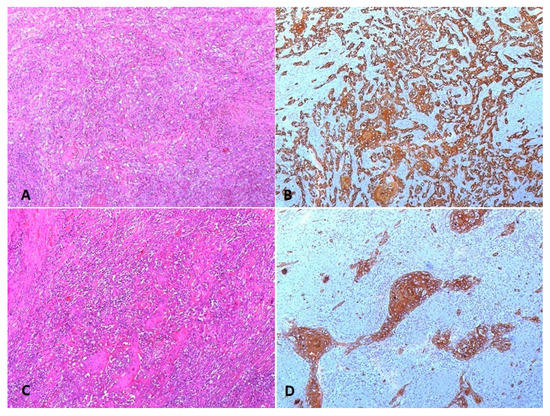

Case Description

3. Results